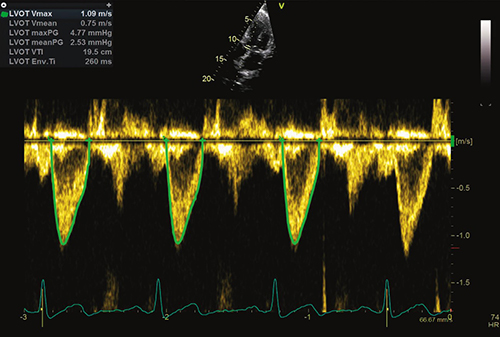

Auto Measure Spectrum Recognition

最新テクノロジーを用いて開発したAuto Measure機能。

2クリックで広範囲のドプラ計測が完了します。Freeze–Measure,2クリックでドプラトレースと関連する計測値のフルセットが瞬時に画面に表示されます。